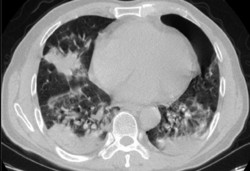

Что коронавирус делает с легкими человека. Наблюдения судмедэксперта из Оша, проводившего вскрытие 3 тел